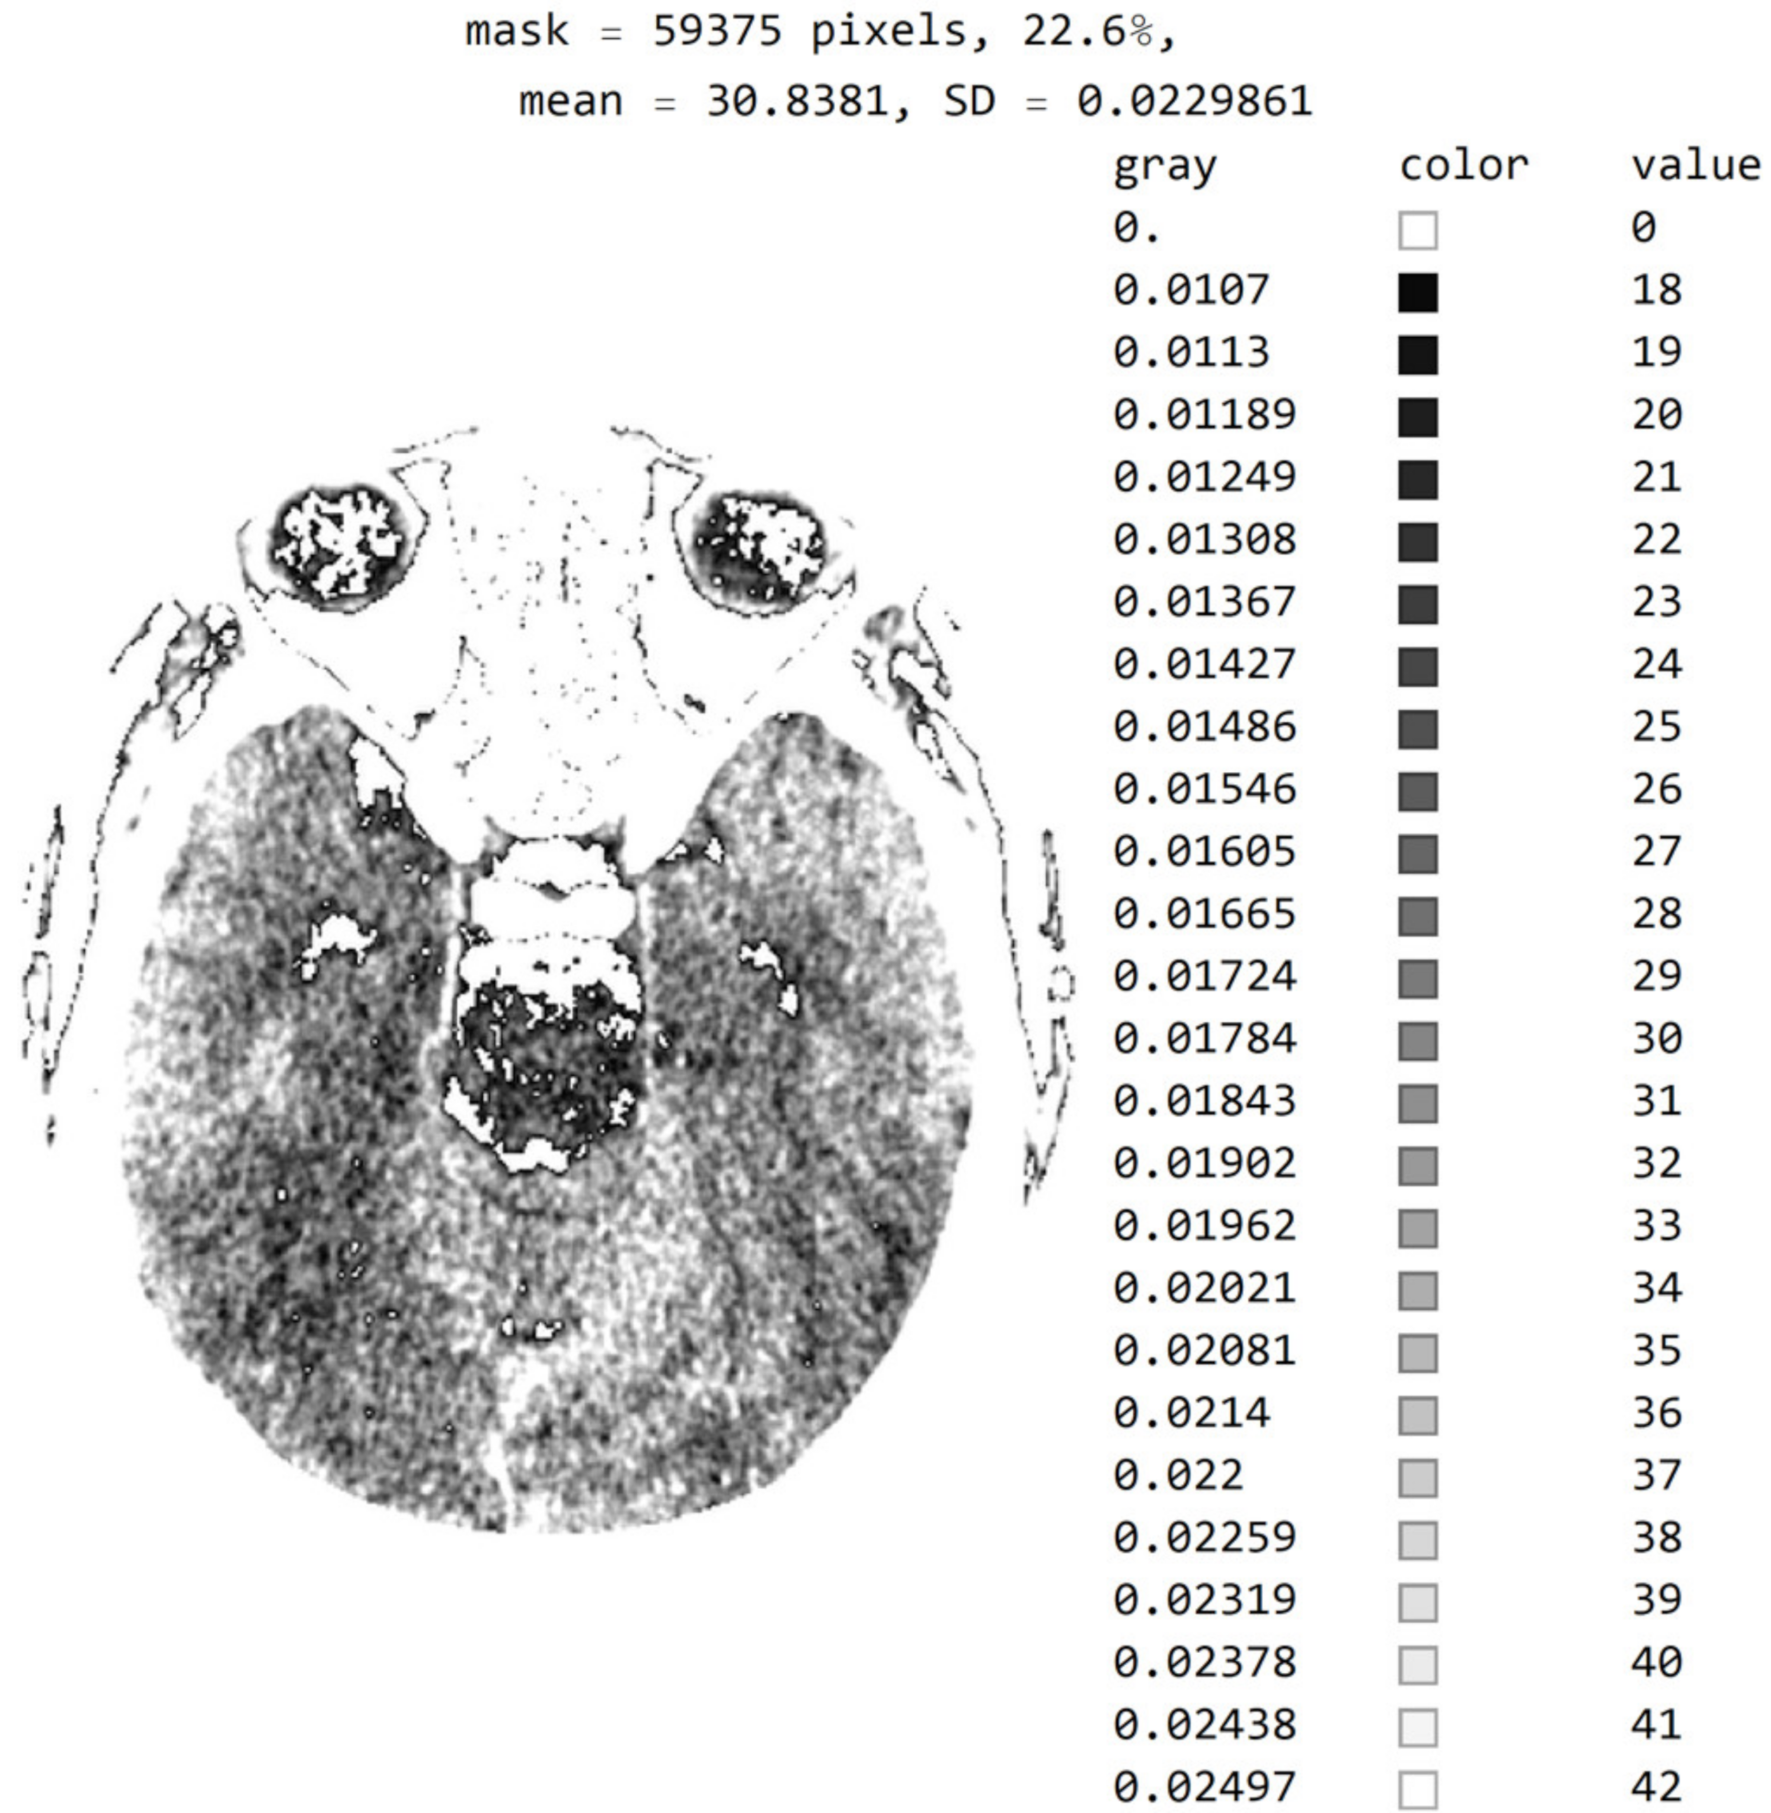

2.2. Smart Visualization Method (SVMI)

3.1. Technological Description